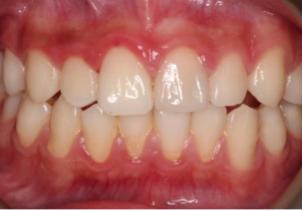

术前:

橡皮障下修复治疗中:

修复术后: